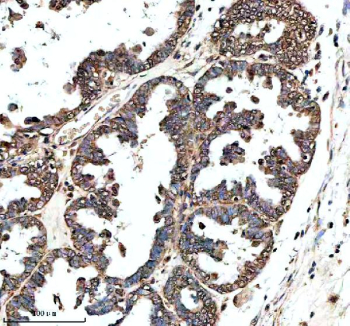

IHC analysis of GHRHR using anti-GHRHR antibody. GHRHR was detected in a paraffin-embedded section of human ovarian cancer tissue. Heat mediated antigen retrieval was performed in EDTA buffer (pH 8.0, epitope retrieval solution). The tissue section was blocked with 10% goat serum. The tissue section was then incubated with 2 ug/ml rabbit anti-GHRHR antibody overnight at 4oC. Peroxidase Conjugated Goat Anti-rabbit IgG was used as secondary antibody and incubated for 30 minutes at 37oC. The tissue section was developed using an HRP secondary and DAB substrate.